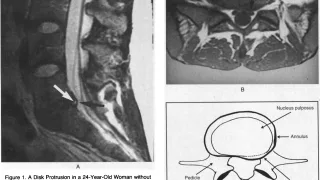

妻の頭痛7時前に起床.昨晩も炬燵で寝落ちしていました.リビングに降りて来た妻が, 「頭が痛い」と訴えました.ズキズキする頭痛とのことで, 自宅にあった頭痛薬マクサルトを内服するように促しました.妻は, 脳腫瘍の既往があり, 頭痛を訴えられる...